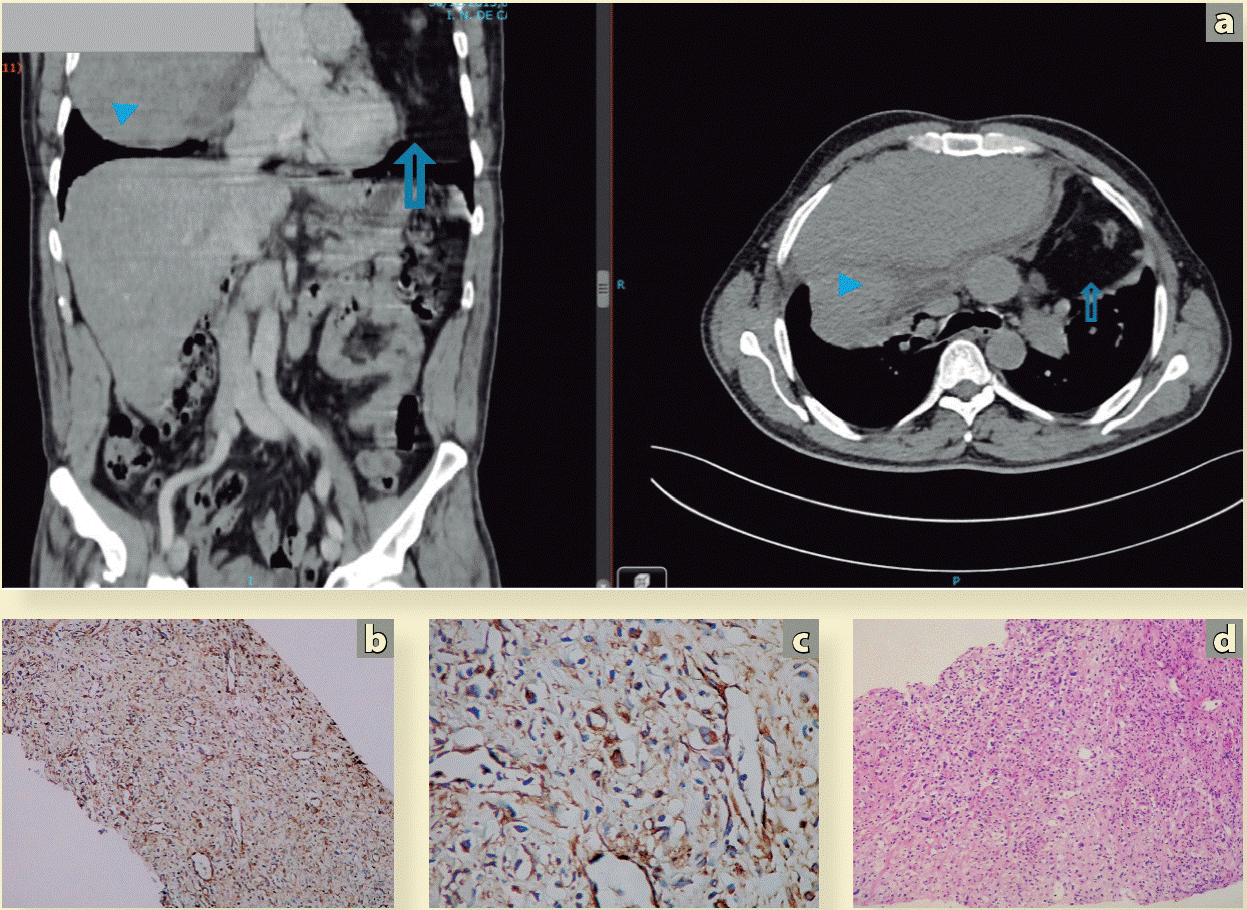

En el caso de un tumor confinado a un hemitórax sugiere que el origen pudiera ser de nervio intercostal posterior. Si el tumor cruza la línea media, el origen puede encontrarse en el tronco simpático, que refleja la encrucijada de las raíces nerviosas y el origen de los nervios intercostales posteriores en el surco paravertebral18. En cuanto a la tomografia por emisión de positrones-tomografía computada (PET-CT), parece tener un valor limitado, pues en poco modifica la conducta terapéutica. Se ha encontrado una relación entre los subtipos histológicos de liposarcoma y el SUVmáx• El liposarcoma bien diferenciado muestra un SUVmáx menor (2.3 ± 1.7) que los subtipos de células mixoides, células redondas y liposarcoma pleomórfico19,20. La biopsia guiada por imagen en manos experimentadas es el estándar de oro para la confirmación histológica, desplazando la biopsia a cielo abierto (Figura 3).

En el paciente comentado en la Figura 2 se realizaron marcadores tumorales para descartar tumor germinal. Fueron negativos: deshidrogenasa láctica, alfafetoproteína, gonadotropiną coriónica humana fracción beta y antigeno carcinoembrionario, a) El paciente fue llevado a biopsia guiada por TAC con aguja de corte, trucut. b) Corte histológico de neoplasia maligna, con patrón de crecimiento sólido. Tinción con hematoxilina y eosina. 100X. Se identifican células fusocelulares con atipia marcada. c) Inmunohistoquímica 100X. Negativo para actina de músculo liso, d) Inmunohistoquímica 400X. Negativa en células neoplásicas para el anticuerpo CD34. También es negativo a los anticuerpos CD 15, CD 30, EMA, S-100, MDM2. Vimentina positivo. Conclusión: sarcoma fusocelular de grado intermedio.

Figura 3 Abordaje diagnóstico de tumor de mediastino, biopsia guiada por tomografia e histopatologia. Tinción con hematoxilina y eosina y técnica de inmunohistoquímica.